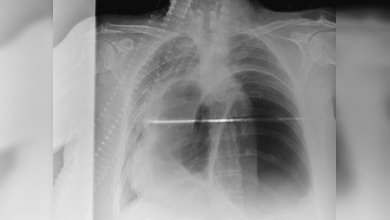

Hace poco, el paciente de cincuenta años, apellidado Van, fue hospitalizado en la ciudad de Shangái con un dolor agudo en el estómago. El examen mostró que en el estómago del hombre se encontraba la mitad de un palillo para comer de madera que, según el mismo paciente, tragó sufriendo un estrés muy grande hacía 28 años.

El objeto ajeno dañó gravemente las paredes estomacales del hombre, lo que causó el empeoramiento de su estado. Los médicos necesitaron varias horas para sacar este 'cubierto' chino del cuerpo del paciente. Ahora, por suerte, se encuentra estable.